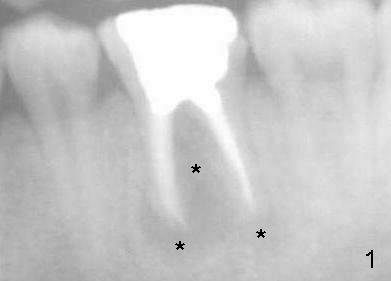

小张,男,22岁,大学刚毕业,忙于找工作,治疗不够积极,左下第一磨牙根管治疗失败,根尖,根分叉阴影(图一*),好像即刻植牙不太合适,建议拔牙后四周,六周之间回来植牙。但是他很拖拉,三个月才回来让我们看看,骨头似乎愈合不错(图二),他又消失五个月,最后还是登门,骨质仿佛继续形成(图三),植入六乘十七毫米植牙(图四,五),舌侧牙龈马上形成cuff(图五**),好像attached gingiva,与邻牙一致(箭头)。您能猜为什么植牙舌侧形成牙龈cuff?

图六是术后十天拍摄,它显示颊侧骨板明显萎缩(箭头),这可能拔牙后形成。由于颊侧骨板萎缩,植牙偏向舌侧,给舌侧牙龈施加压力,便形成牙龈cuff。